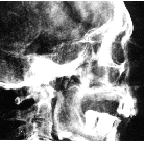

En la imagen :

Merenptah, hijo de Ramesses II, y la Reina Isis-nofret I .

De prominente, y redondeada glabella . Frente baja, e inclinada ; meseta sagital; ANB alto y overbite; barbilla retruida. El ramus algo largo, la mandíbula levemente angular y el arco cigomatico proyectado hacia adelante recuerdan a su padre Ramesses II.